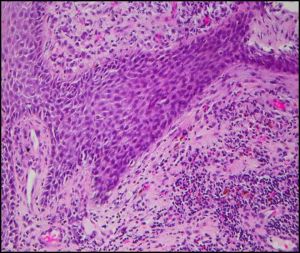

形態學:

主要形態學特點是在合適的背景中區分出郎格罕斯細胞。郎格罕斯細胞大約有10-15微米,組織學上可以通過特徵性的有溝的、摺疊的、凹折的或分葉狀的核,染色質細膩、有不太清晰的核仁、核膜薄。可以出現核的非典型性,但是如出現明顯的惡性的細胞學特徵時,應傾向考慮為郎格罕斯細胞肉瘤,下面會討論。核分裂相數目變化很大。細胞的胞漿通常中等豐富、輕度嗜酸性。特徵性的背景通常包括數量不等的嗜酸性粒細胞、組織細胞(包括多核細胞型,常呈骨巨細胞樣)、中性粒細胞和小淋巴細胞。偶爾會發現伴有中央壞死的嗜酸性粒細胞膿腫。病變早期,常見到大量的郎格罕斯細胞、嗜酸性和中性粒細胞,然而晚期病變常呈嚴重的纖維化,常包含泡沫樣巨噬細胞。淋巴結受累時最先出現在竇內、繼而出現在副皮質區,然而在脾臟最易累及紅髓。當郎格罕斯細胞增生症常與惡性淋巴瘤伴發時,經常小灶性地出現在淋巴瘤腫瘤內或旁。骨髓的累及的在活檢時比塗片時更易發現,常由小灶性的病變組成,可以伴有纖維化。